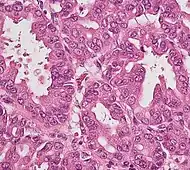

Histopathology

The most common form of pancreatic cancer (adenocarcinoma) is typically characterized by moderately to poorly differentiated glandular structures on microscopic examination. There is typically considerable desmoplasia or formation of a dense fibrous stroma or structural tissue consisting of a range of cell types (including myofibroblasts, macrophages, lymphocytes and mast cells) and deposited material (such as type I collagen and hyaluronic acid). This creates a tumor microenvironment that is short of blood vessels (hypovascular) and so of oxygen (tumor hypoxia).[2] It is thought that this prevents many chemotherapy drugs from reaching the tumor, as one factor making the cancer especially hard to treat.[2][3]

| Cancer type | Relative incidence[11] | Microscopy findings[11] | Micrograph | Immunohistochemistry markers[11] | Genetic alterations[11] |

|---|---|---|---|---|---|

| Pancreatic ductal adenocarcinoma (PDAC) | 90% | Glands and desmoplasia | ![]() | ||

| Pancreatic acinar cell carcinoma (ACC) | 1% to 2% | Granular appearance | ![]() |